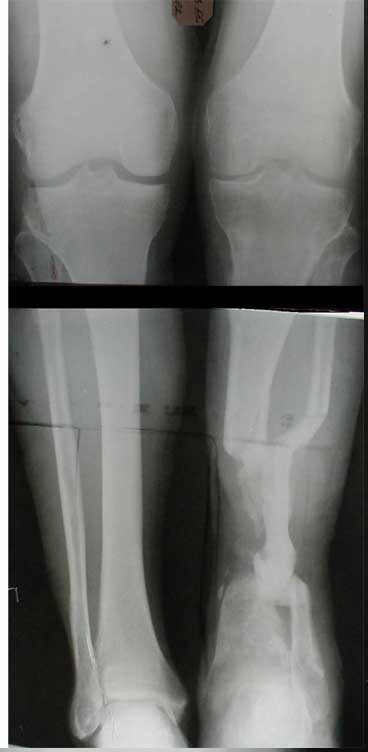

В приложении - моё наблюдение (возможно, уже представлял, тогда

извините).

Нога попала в пресс.

Ко мне больной попал черз 1,5-2 года после травмы и нескольких

операций с синегнойной инфекцией на всю голень. Меня пригласили на консультацию

насчет ампутации.

Лечил я его месяцев 8.

Малоберцовка полностью перестроилась, нога опороспособна.

При ходьбе на дальние расстояния пользуется тростью.

Осталась трофическая язва, периодически закрывается.

Клинические снимки где-то есть, но не очень качественные.

Один из вариантов.

С уважением Александр Артемьев

К сожалению на первичной и последующей рентгенограммах не видно, что творится с голеностопным суставом. Если вилка суства сохранена, то есть смысл побороться за конечность. Интересно, увитеть, что твориться с голеностопным суставом.